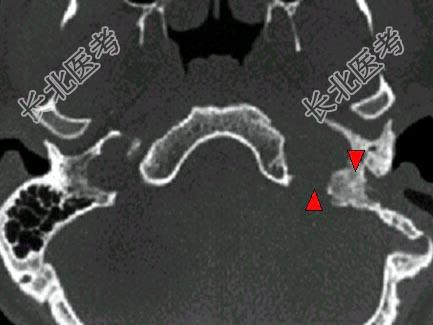

- 单项选择题男,45岁, 左侧搏动性耳鸣半年,耳镜检查透过鼓膜后下部见半膨隆紫红色肿物, CT如图,最可能的诊断是 ( )

E、颈静脉球瘤